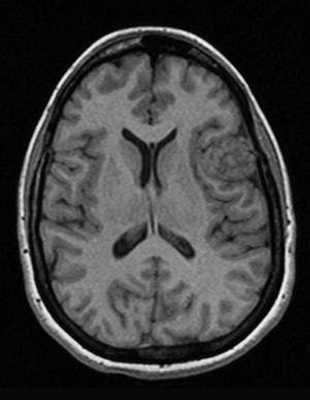

Классический пример МРТ снимков головного мозга показан на рисунках ниже. Магнитно-резонансная томография выполняется в поперечной (или аксиальной - рисунок снизу) и продольной (или сагиттальной — рисунок сверху) плоскостях.

Исследование выполняется в нескольких режимах. Основные из них Т1 и Т2. Изображения, полученные в данных режимах, часто также называют Т1-взвешенными или Т2-взвешенными снимками. Изображения, показанные выше, сделаны в Т1-режиме.

Главное отличие этих режимов - в том, как на снимках отображается жидкость и воздух. В Т1 режиме ткани, содержащие большое количество воды, имеют более темную окраску, в то время как в Т2 режиме они яркие, светлые. Это легко понять, посмотрев на снимки выше - глазные яблоки визуализируются в виде светлых парных округлых образований с одной стороны яркие и светлые, с другой - темные. Следовательно, снимок справа сделан в Т1 режиме, снимок слева - в Т2. Также существует разница в том, как в этих режимах отображается серое вещество головного мозга. В Т2 режиме оно светлее, чем белое вещество.